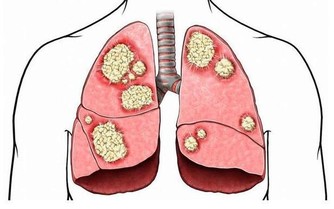

但是如果我們食用過量的蘿蔔乾,就很容易患上胃癌等疾病。